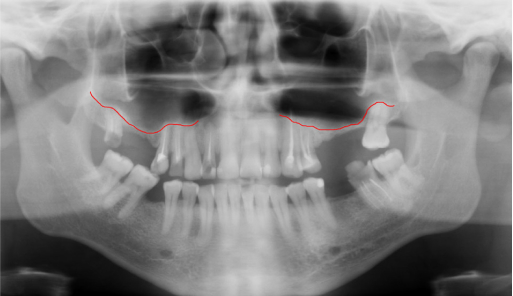

Before